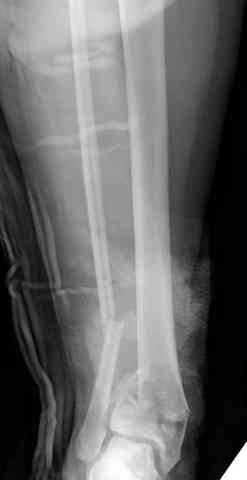

Снова приветствую вас, коллеги. К моменту вступления в обсуждение аксакалов, операция была, увы, выполнена(31.10.07.) Начали с доступа к наружной лодыжке, произвели ее фиксацию спицами, развернули кусок заднего края, наложили дистрактор, затем произвели дистракцию, фиксацию спицами дистального эпиметафиза б/бк,Рентгено-контроль. синтез наружной лодыжки 1/3пластиной. из двух коротких разрезов сформирован канал под медиальную тибиальную пластину LCP. Края ран ушиты без натяжения. Прочувствовать жесткость фиксации винтами с угловой стабильностью не удалось, поэтому дистрактор оставлен на энное время.

На представленных R-снимках не окончательный вид после остеосинтеза. Дистальная опора давила на стопу, пришлось ее сместить проксимально, в рез-те чего, она закрыла щель сустава, последние снимки не информативны.

Нижний винт, похоже, длинноват.

Дистальные винты как-то чуть не все идут не в дистальные отломки, а в зону перелома. И действительно, присоединяюсь к вопросу Якова - в диафизе так и оставили 1 винт?